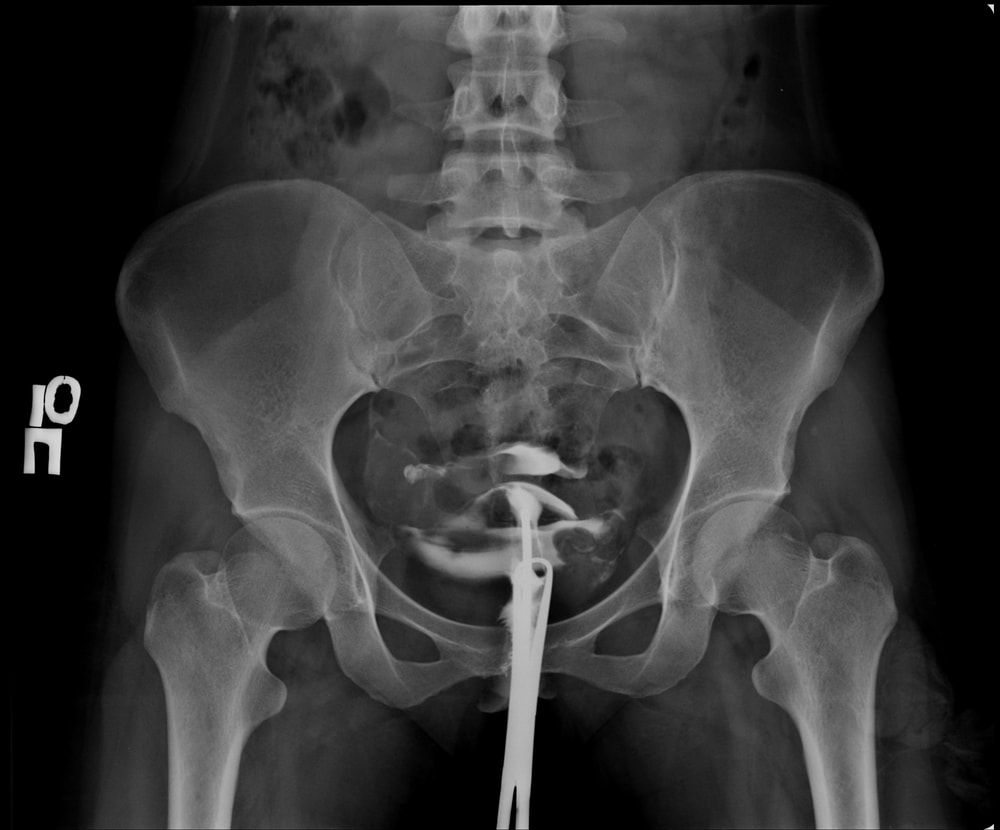

У меня похожий снимок. И у меня одна труба проходима, но извилистая очень. Вторая непроходима.

К вас одна труба точно проходима. Видно что контрастное вещество излилось

«Трубы прослеживаются»👉 контраст заполняет маточные трубы - они не перекрыты на входе.

«Эвакуация есть»👉 контраст выходит из труб в брюшную полость - это главный признак проходимости.

«Проба Котта положительная»👉 положительная проба Котта подтверждает проходимость труб (контраст свободно прошёл через них).

✅ Маточные трубы проходимы (по данным ГСГ).Минимум одна труба проходима, а чаще - обе, если в заключении не указано иное.